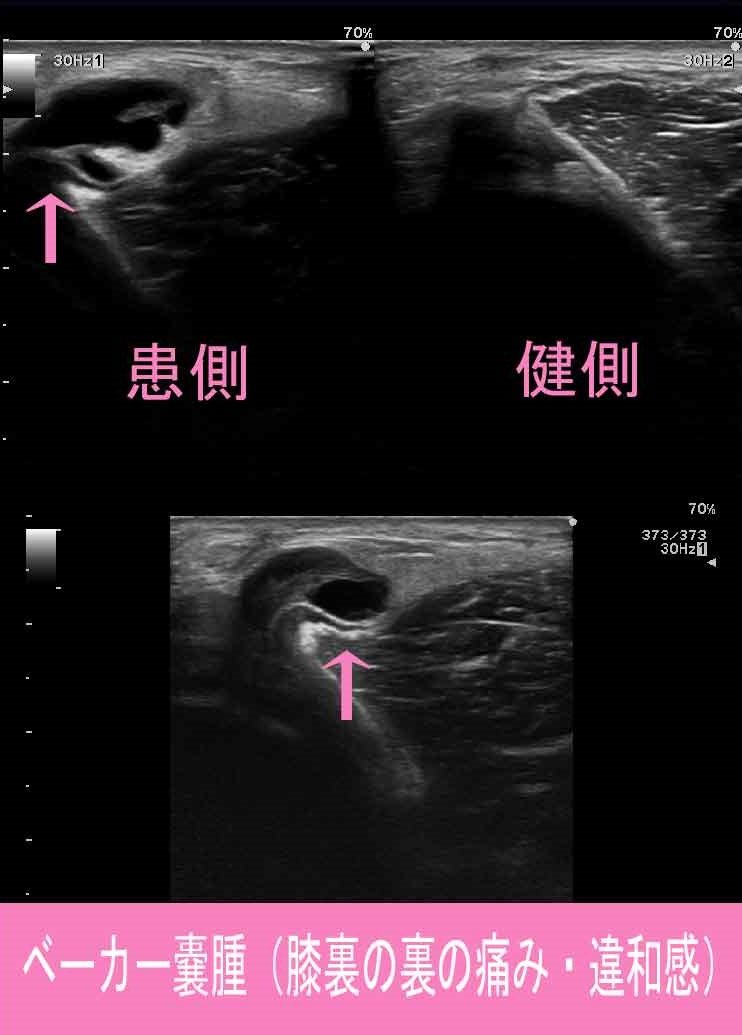

原因は、膝関節部が腫れる変形性膝関節症・半月板損傷

関節リウマチ・関節炎などの炎症反応により関節内部に多量の滑液が生じることで、

ベーカー嚢腫が大きくなります。

ベーカー嚢腫が大きく屈曲制限が強い場合は、針を刺して滑液を抜き取ります。

滑液を抜き取っても再度大きくなってしまう場合は、

手術でベーカー嚢腫を切除することも考えます。

ベーカー嚢腫2.jpg